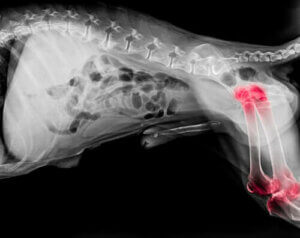

Eksperter mener, at omkring en ud af fem hunde lider af gigt. Selvom denne lidelse kan opstå i enhver alder, er det mere gængst hos ældre hunde. Generelt sagt, er gigt en degenerativ lidelse, som forårsager betændelse i både leddene ved skuldre og albuer.